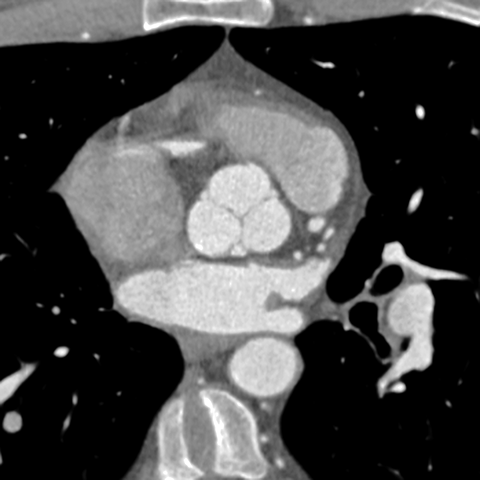

Aortic Valve (CT) [3 of 5]